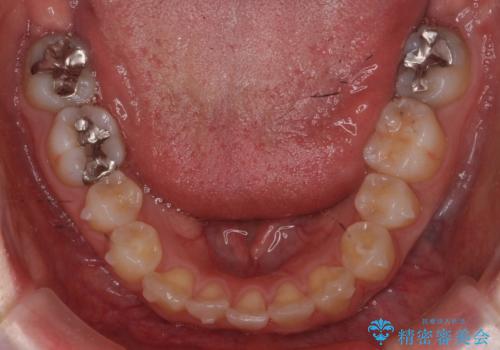

下の前歯が生まれつき3本でした。

下を3本でそのまま並べてあるため、上下の正中は合いません。

合わせようとすると抜歯か、下の隙間を無理やり開けてブリッジとなりますが、そこまでするメリットがないため、下はそのままの歯の数を生かしています。